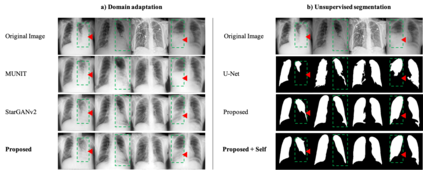

As the segmentation labels are scarce, extensive researches have been conducted to train segmentation networks without labels or with only limited labels. In particular, domain adaptation, self-supervised learning, and teacher-student architecture have been introduced to distill knowledge from various tasks to improve the segmentation performance. However, these approaches appear different from each other, so it is not clear how these seemingly different approaches can be combined for better performance. Inspired by the recent StarGANv2 for multi-domain image translation, here we propose a novel segmentation framework via AdaIN-based knowledge distillation, where a single generator with AdaIN layers is trained along with the AdaIN code generator and style encoder so that the generator can perform both domain adaptation and segmentation. Specifically, our framework is designed to deal with difficult situations in chest X-ray (CXR) segmentation tasks where segmentation masks are only available for normal CXR data, but the trained model should be applied for both normal and abnormal CXR images. Since a single generator is used for abnormal to normal domain conversion and segmentation by simply changing the AdaIN codes, the generator can synergistically learn the common features to improve segmentation performance. Experimental results using CXR data confirm that the trained network can achieve the state-of-the art segmentation performance for both normal and abnormal CXR images.